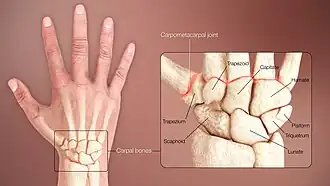

Joints

| Name | Proximal/radial articulations |

Lateral/medial articulations |

Distal/metacarpal articulations |

|---|---|---|---|

| Proximal row | |||

| Scaphoid | radius | capitate, lunate | trapezium, trapezoid |

| Lunate | radius, articular disk | scaphoid, triquetral | capitate, hamate (sometimes) |

| Triquetrum | articular disk | lunate, pisiform | hamate |

| Pisiform | triquetral | ||

| Distal row | |||

| Trapezium | scaphoid | trapezoid | first and second metacarpal |

| Trapezoid | scaphoid | trapezium, capitate | second metacarpal |

| Capitate | scaphoid, lunate | trapezoid, hamate | third, partly second and fourth metacarpal |

| Hamate | triquetral, lunate | capitate | fourth and fifth |